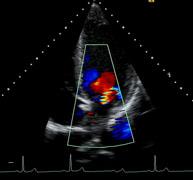

The cardiology upgrades improve clinical confidence and increase workflow efficiency with a number of advanced applications. Dynamic TCE tissue contrast enhancement technology is a powerful new algorithm, which provides advanced speckle reduction and enhanced contrast resolution for more detailed images, and is now available on all phased array transducers. The Acuson S2000 system, release 2.0 can perform intracardiac echocardiography (ICE) with the Acuson AcuNav ultrasound catheter. Live dual display functionality enables simultaneous viewing of B-mode and color Doppler images with the push of a single button, eliminating extra keystrokes and improving workflow efficiency.